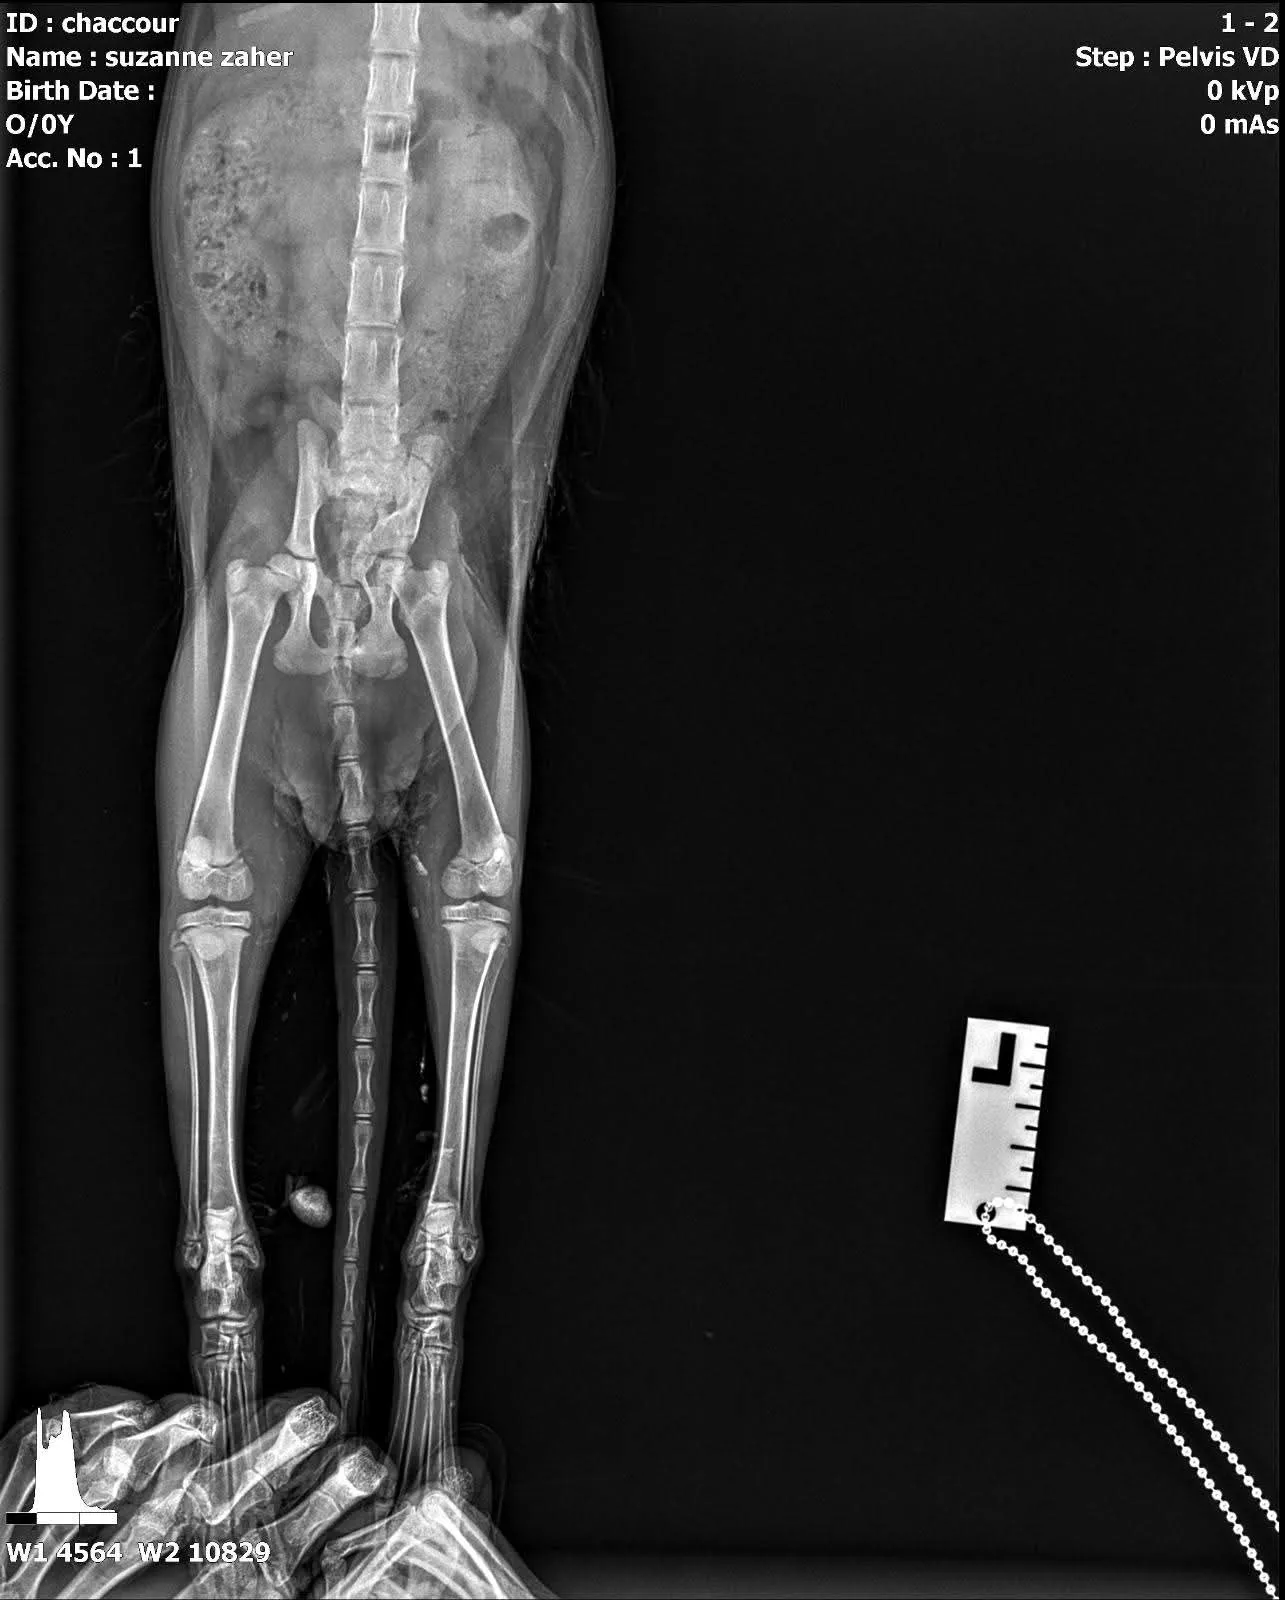

A surgical procedure for a pelvic fracture in cat